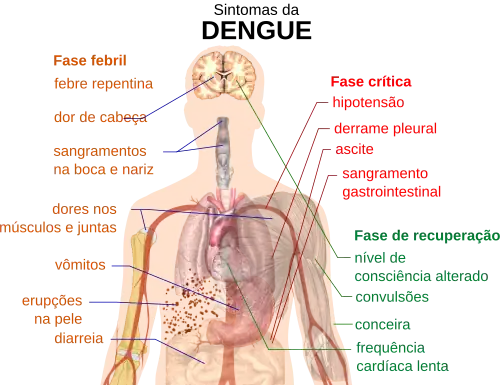

Os sintomas característicos da dengue são febre de início súbito, dor de cabeça (normalmente localizada atrás dos olhos), dores musculares e articulares, além de erupções cutâneas. O nome alternativo para a dengue, "febre quebra-ossos", vem da dor causada em músculos e articulações.[12][19] O curso da infecção é dividido em três fases: febril, crítica e de recuperação.[20]

A fase febril envolve febre alta, potencialmente acima de 40 °C, associada a dor de cabeça e dor generalizada; esta fase geralmente dura de dois a sete dias.[19][20] Podem também ocorrer vômitos.[9] A erupção ocorre em 50 a 80% dos pacientes[19][21] no primeiro ou no segundo dia de sintomas, como pele corada, ou mais tarde no curso da doença (dias 4-7), como uma erupção morbiliforme, (semelhante a causada pelo sarampo).[21][22] Algumas petéquias (pequenas manchas vermelhas que não desaparecem quando a pele é pressionada, as quais são causadas por ruptura de capilares) podem aparecer nesta fase,[20] assim como algum sangramento leve da membrana mucosa da boca e do nariz.[17][19] A febre em si é classicamente de natureza bifásica, depois é interrompida e, em seguida, volta durante um ou dois dias, embora muitas vezes haja grande variação na forma como este padrão realmente acontece em cada pessoa.[11][22]

Em algumas pessoas, a doença prossegue para uma fase crítica logo após o período de intervalo da febre[9] e, normalmente, durando de um a dois dias.[20] Durante esta fase, pode haver acumulação significativa de fluido nas cavidades torácica e abdominal, devido ao aumento da permeabilidade e do vazamentos dos capilares sanguíneos. Isto leva à depleção de fluido a partir da circulação e hipoperfusão, a diminuição do fornecimento de sangue para os órgãos vitais.[20] Durante esta fase, pode ocorrer a disfunção de órgãos e sangramentos graves, normalmente a partir do trato gastrointestinal.[17][20] SCD (síndrome do choque da dengue) e hemorragias (dengue hemorrágica) ocorrem em menos de 5% de todos os casos de dengue.[17] No entanto aqueles que tenham sido previamente infectados com outro sorotipo do vírus da dengue ("infecção secundária") têm um risco aumentado.[17][23] Essa fase crítica, apesar de rara, geralmente ocorre mais em crianças e em adultos jovens.[9] A febre hemorrágica da dengue (FHD) e a síndrome de choque da dengue (SCD) atingem pelo menos 500 mil pessoas todos os anos e apresentam uma taxa de mortalidade de até 10% para pacientes hospitalizados e de 30% para pacientes que não receberam tratamento.[6]

A fase de recuperação ocorre em seguida, com a reabsorção do líquido que vazou para a corrente sanguínea.[20] Isso geralmente dura de dois a três dias.[17] A melhora é muitas vezes surpreendente e pode ser acompanhada por grave coceira e por uma frequência cardíaca lenta.[17][20] Outra erupção pode ocorrer, seja maculopapular ou vasculítica, que é seguida por uma descamação da pele.[9] Durante esta fase, pode ocorrer um estado de sobrecarga de líquidos que, se afetar o cérebro, pode causar um redução do nível de consciência ou convulsões no paciente.[17] A sensação de fadiga pode durar algumas semanas em adultos.[9]